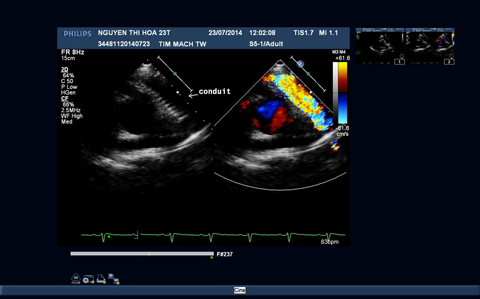

Sau phẫu thuật, hồi sức cho bệnh nhân gặp rất nhiều khó khăn do tình trạng suy thất phải gây giảm cung lượng tim. Tình trạng bệnh nhân cuối cùng đã cải thiện, các dấu hiệu suy tim phải giảm dần, SpO2 cải thiện từ 85% trước mổ lên 94%, trên điện tâm đồ nhịp xoang đều không có các rối loạn nhịp, trên siêu âm tim (Hình 3) vách liên thất kín, động mạch chủ chỉ thông thương với thất trái, ống mạch nhân tạo thông tốt, không còn ống động mạch và có hình ảnh lỗ thông liên nhĩ nhân tạo shunt trái phải và bệnh nhân đã được xuất viện.

Hình 3: Hình ảnh siêu âm tim trước và sau phẫu thuật

3B: Hình ảnh đoạn mạch nhân tạo thông tốt giữa thất phải và hội lưu động mạch phổi.